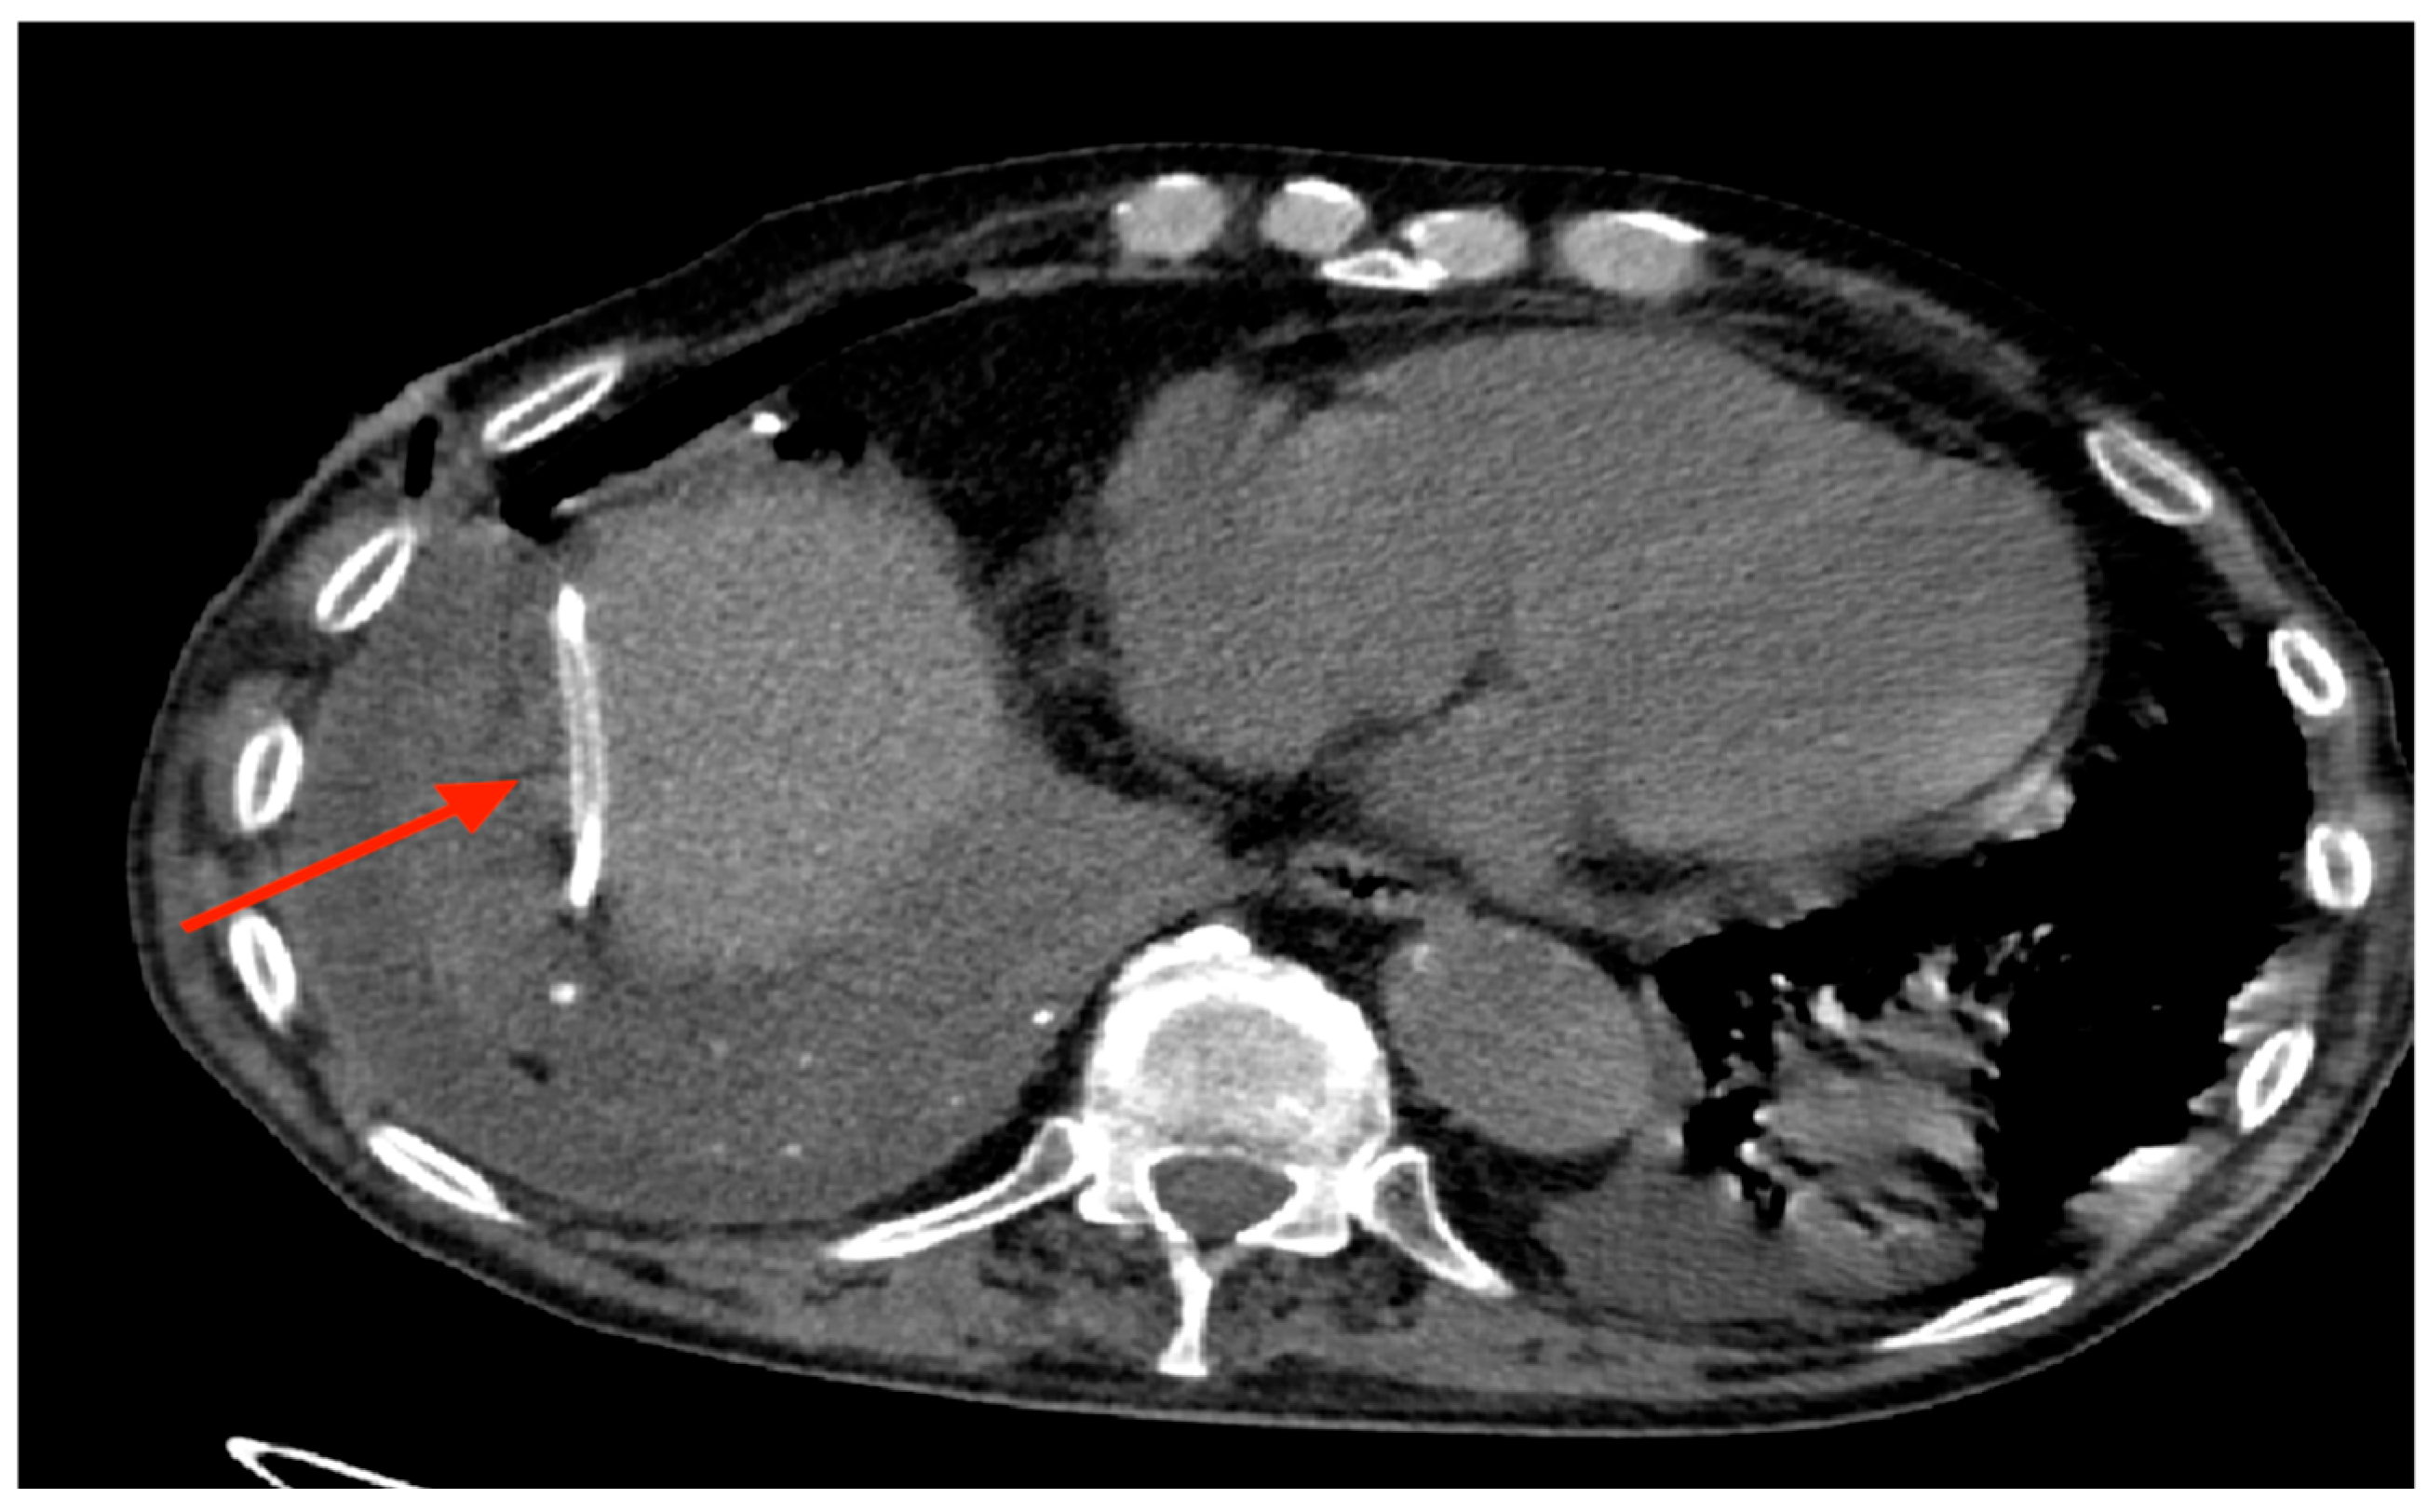

Out of 150 patients, there was a single case in which the drainage tube was implanted in the abdomen (Figure 7) and only one case of total post-implantation pneumothorax, as shown by Figure 8-A and 8-B, which however didn’t require an additional chest drainage tube and was resolved by connecting the port to a digital suction system. During follow up 18 (12%) patients developed complications (Table 3), mainly in the trapped lung sub-group (9%), with malfunction (and thus failure) of the device and wound dehiscence as the most represented ones.

There was only one case of wrong placement of the device, with the drainage tube implanted in the abdomen, between the diaphragm and the liver. The device was readily repositioned in the correct location, without any consequences for the patient.

Figure 7. Drainage tube implanted between diaphragm and liver.